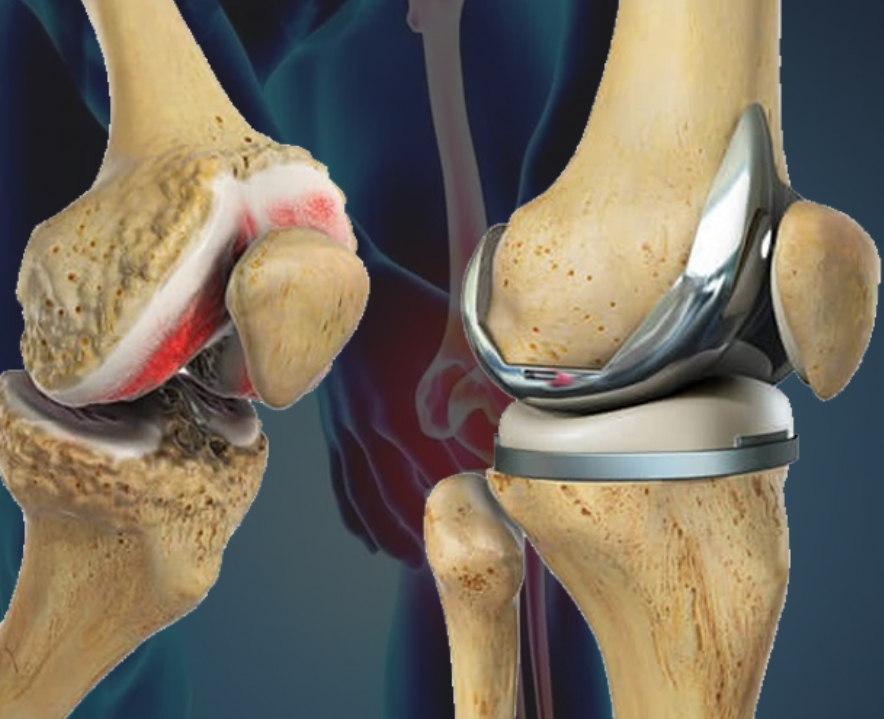

Read MoreDr. Praveen Chaudhary is a highly skilled orthopedic surgeon with over 10,000 successful surgeries and more than a decade of expertise in trauma management, joint replacement, and arthroscopic procedures. He specializes in Total Knee and Hip Replacements (TKR & THR), ACL/PCL reconstructions, meniscus and rotator cuff repairs, and spinal trauma.

With 10+ years of experience in joint replacement, arthroscopy, and trauma cases, Dr. Praveen Chaudhary is known for his advanced surgical skills and personalized treatment approach, ensuring faster recovery and long-lasting relief: